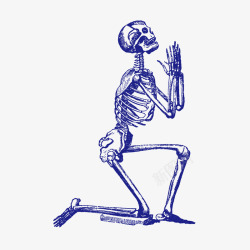

人体骨骼组织结构图

手绘人体骨骼结构图